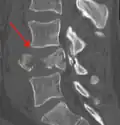

Burst fracture

A burst fracture is a type of traumatic spinal injury in which a vertebra breaks from a high-energy axial load (e.g., traffic collisions or falls from a great height or high speed, and some kinds of seizures), with shards of vertebra penetrating surrounding tissues and sometimes the spinal canal.[1] The burst fracture is categorized by the "severity of the deformity, the severity of (spinal) canal compromise, the degree of loss of vertebral body height, and the degree of neurologic deficit."[2] Burst fractures are considered more severe than compression fractures because long-term neurological damage can follow. The neurologic deficits can reach their full extent immediately, or can progress for a prolonged time.